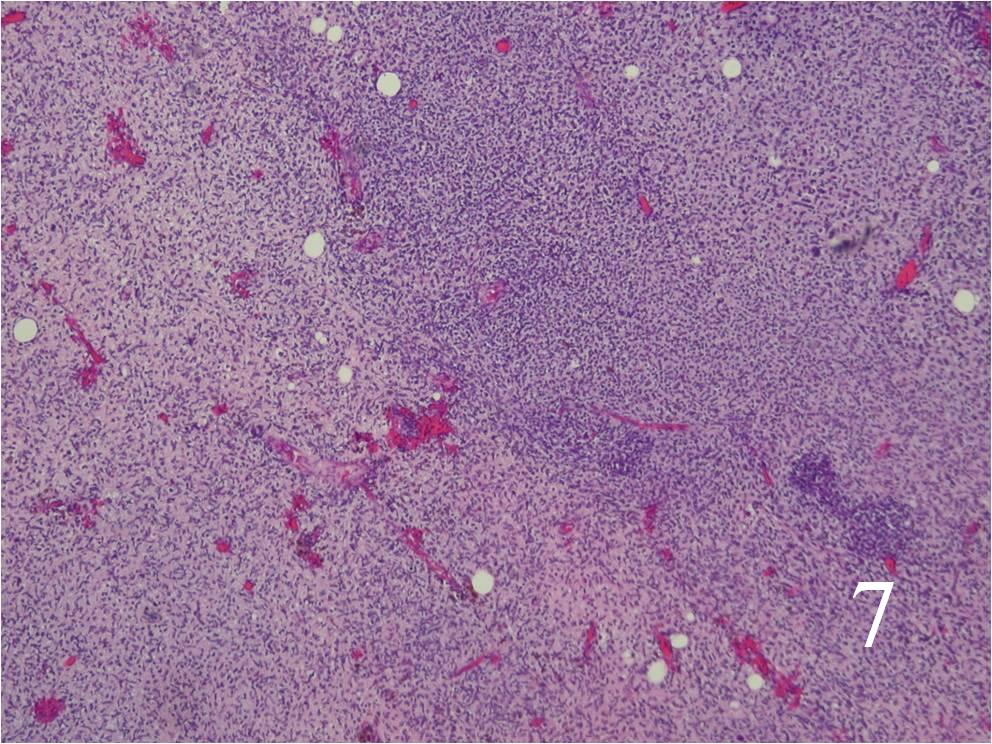

Microscopic

- Resembles fibrosarcomas

- Usually high grade features

- Spindle cells with markedly irregular contours (Fig. 7, 8)

- Nuclei are comma-shaped

- Cells are arranged in sweeping fascicles

Fig. 7 Low power and high power (Fig. 8) magnification on H&E staining shows a spindle cell neoplasm with high cellularity, abnormal mitotic features and nuclear atypia. The cells are arranged in a somewhat fascicular manner.